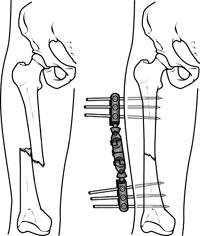

تثبيت الكسور بالشرائح والمسامير

ومع تقدم العلم اختلفت أنواع تثبيت الكسور جراحيًا تبعًا لنوع الكسر ومكانه ، وأيضًا تبعًا لعمر المريض وضمن هذه الأنواع هي تركيب الشرائح والمسامير الطبية، وتركيب المثبتات الخارجية والمسامير النخاعية ويحتاج الطبيب المعالج لعمل بعض الأشعات اللازمة لتحديد النوع المناسب لتثبيت الكسور.

ويقوم الطبيب بتثبيت الكسور والشروخ في جسم الإنسان بواسطة تركيب شرائح طبية ومسامير تساعد على التئام الكسر بشكل طبيعي وفي مكانه الصحيح مما يضمن للمريض استعادة حياته اليومية بشكل سريع وبدون ألم. وتناسب هذه الشرائح والمسامير بصفة خاصة الكسور القريبة من المفاصل.

تنبيه: لا يستحب تركيب الشرائح في حالة وجود تلوث حول الجرح نتيجة للحوادث التي تعرض لها المريض، وفي هذه الحالات يستحب استخدام المثبتات الخارجية